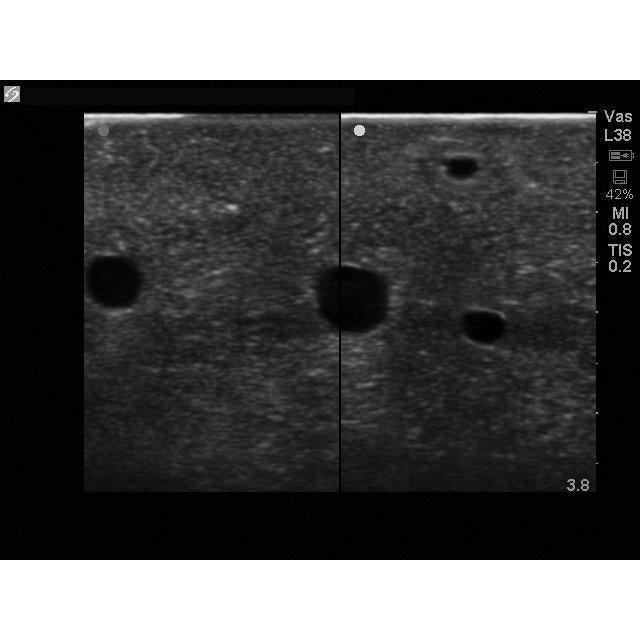

Our Branched 4 Vessel ultrasound guided vascular access training model contains a blood vessel that branches into 4 vessels positioned at differing depths and course throughout the model. Users can image the bifurcating vessels, track the course of the vessels, and guide needles into the targeted vessel using ultrasound imaging. Clinicians can gain experience acquiring and interpreting ultrasound images of blood vessels as well as developing the psychomotor skill associated with guiding needles to simulated vessels.

Our Branched 4 Vessel ultrasound guided vascular access training model contains a blood vessel that branches into 4 vessels positioned at differing depths and course throughout the model. Users can image the bifurcating vessels, track the course of the vessels, and guide needles into the targeted vessel using ultrasound imaging. Clinicians can gain experience acquiring and interpreting ultrasound images of blood vessels as well as developing the psychomotor skill associated with guiding needles to simulated vessels.

- Contains four vessels of various sizes including 4mm, 6mm, and 8mm branched vessels positioned at a variety of depths within the phantom

- Learn to acquire and interpret imaging of vessels used for venipuncture